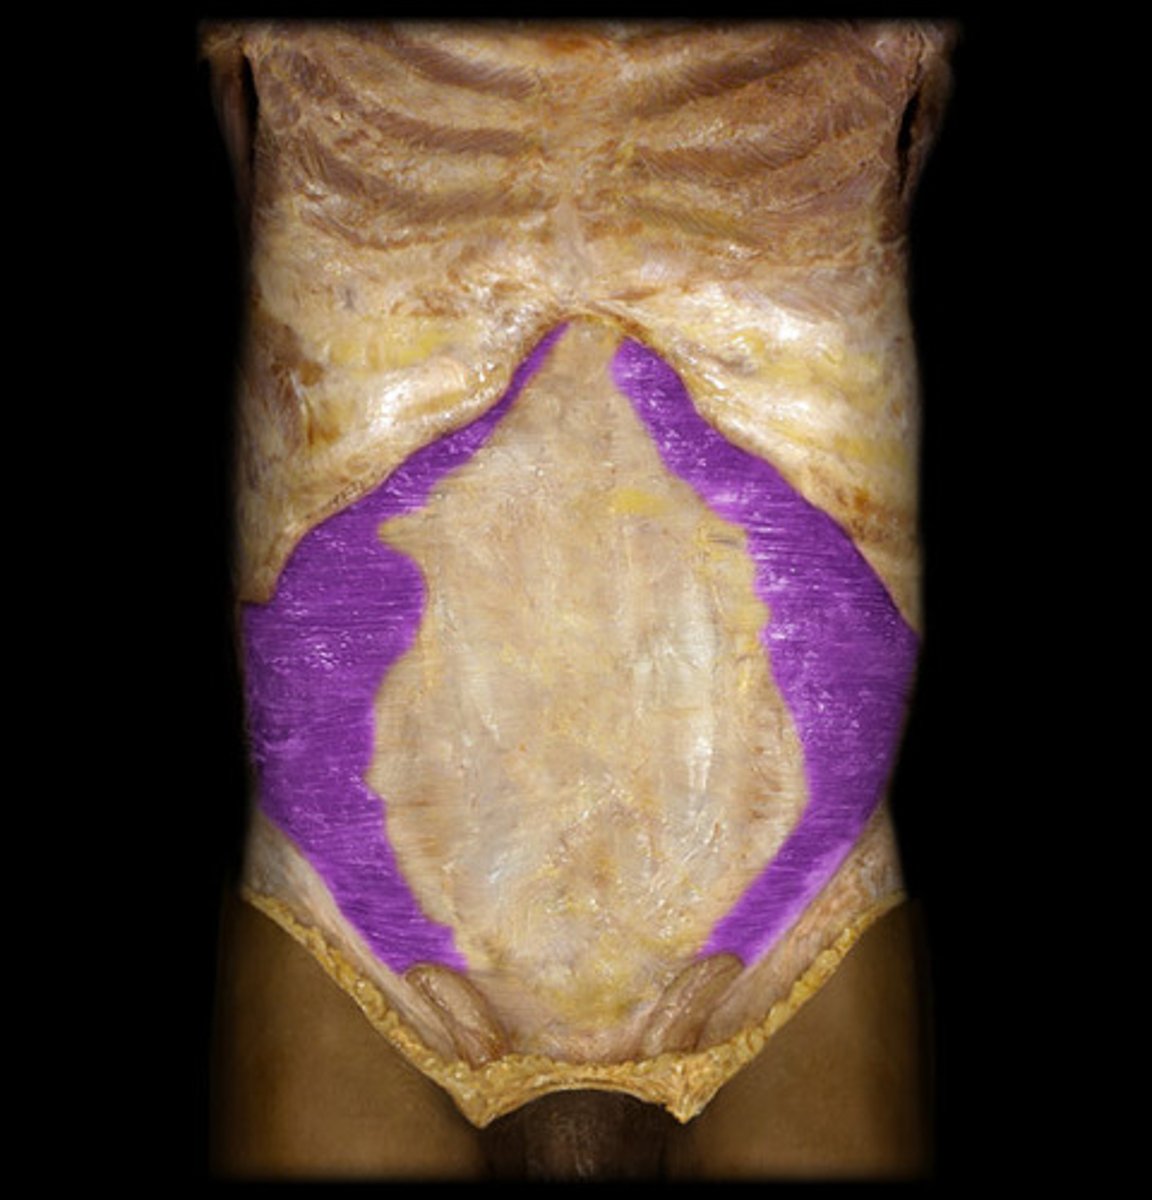

External oblique

Internal oblique

Transverse abdominis

Rectus abdominis